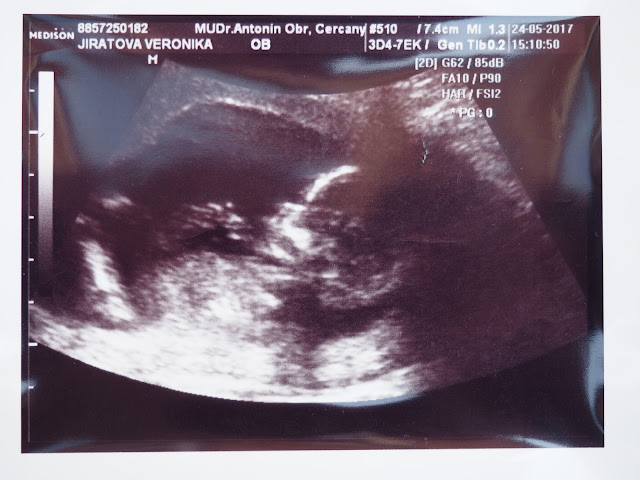

Součástí vyšetření neboli

screeningu je i ultrazvuk, kde mi ukázal ručičky, nožičky, žaludek, páteř,

močový měchýř a pustil nám s přítelem srdíčko. Pro ty znalejší Vám

přiložím fotku výsledku z vyšetření. Já si z toho odnesla jen to, že

čím větší číslo tím lepší.